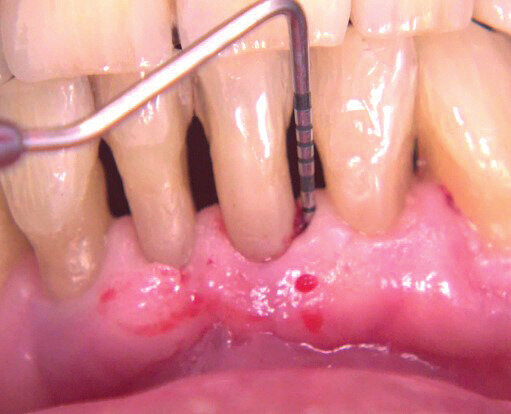

Il paziente di anni 33 viene inviato per trattamento di un gonfiore gengivale apparso circa 1 mese prima. È stato trattato con scaling e root planing senza ottenere il risultato voluto. All’esame obiettivo presenta una lieve gengivite interprossimale con infiammazione e gonfiore limitato alla parte vestibolare di 2.1 con sondaggio di 5 mm vestibolare e 7 mm disto-vestibolare (Fig. 1). La superficie della radice era stata strumentata una settimana prima e si presenta senza residui di tartaro e senza riassorbimenti esterni. Viene scelta l’applicazione di Ozosan Gel per ridurre subito i sintomi che limitavano la capacità del paziente di applicare una corretta igiene orale e per la sua azione antibatterica ma anche stimolante la guarigione. Ozosan Gel viene applicato per 8 minuti - azione anti batterica - seguito da lavaggio con fisiologica. Da subito il paziente segnala riduzione del dolore e viene istruito a uno spazzolamento delicato a roll con spazzolino morbido. Viene rivisto dopo 2 giorni ed effettuata una nuova applicazione di ozono. Controllo a 5 gg (Fig. 2), e applicazione di Ozosan Gel per due minuti per stimolare la guarigione (Fig. 3). Controllo a 2 sett. (Fig. 4) dove si nota recessione dei tessuti che erano stati strumentati in modo aggressivo. Guarigione a due mesi dove i tessuti stanno ricoprendo la recessione (Fig. 5).

Fig. 1 - Aspetto clinico del paziente alla prima visita. Viene applicato Ozosan® per 8 min e lavato con fisiologica.